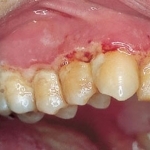

- Đừng để nha chu qua giai có túi nướu (Pockets)

- Đừng để bệnh nha chu tiến triển sang đoạn 3 (tiêu xương ổ răng là răng bị lung lay) sẽ khó hồi phục.